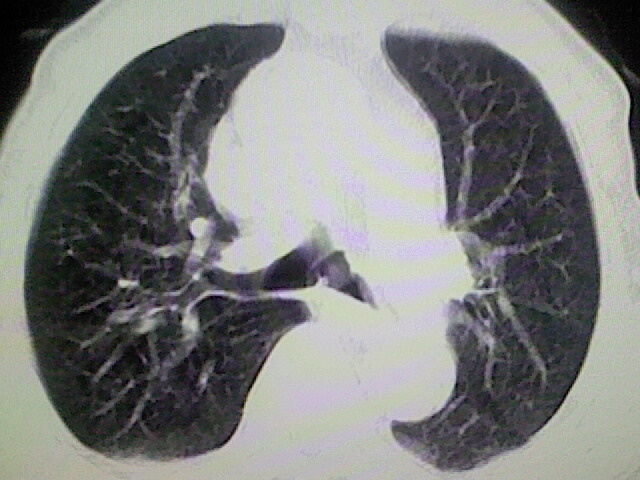

以下是引用zsl6918在2008-8-28 16:49:00的发言:[br]双肺炎性病灶,食管狭窄估计与心房增大压迫所致。

以下是引用xulianj在2008-8-28 20:36:00的发言:[br]慢支肺气肿伴感染,右上肺陈旧性结核;食道建议胃镜检查。

以下是引用wqs571018在2008-8-28 21:18:00的发言:[br]慢支继发感染,右上肺陈旧性结核;食道建议胃镜检查。